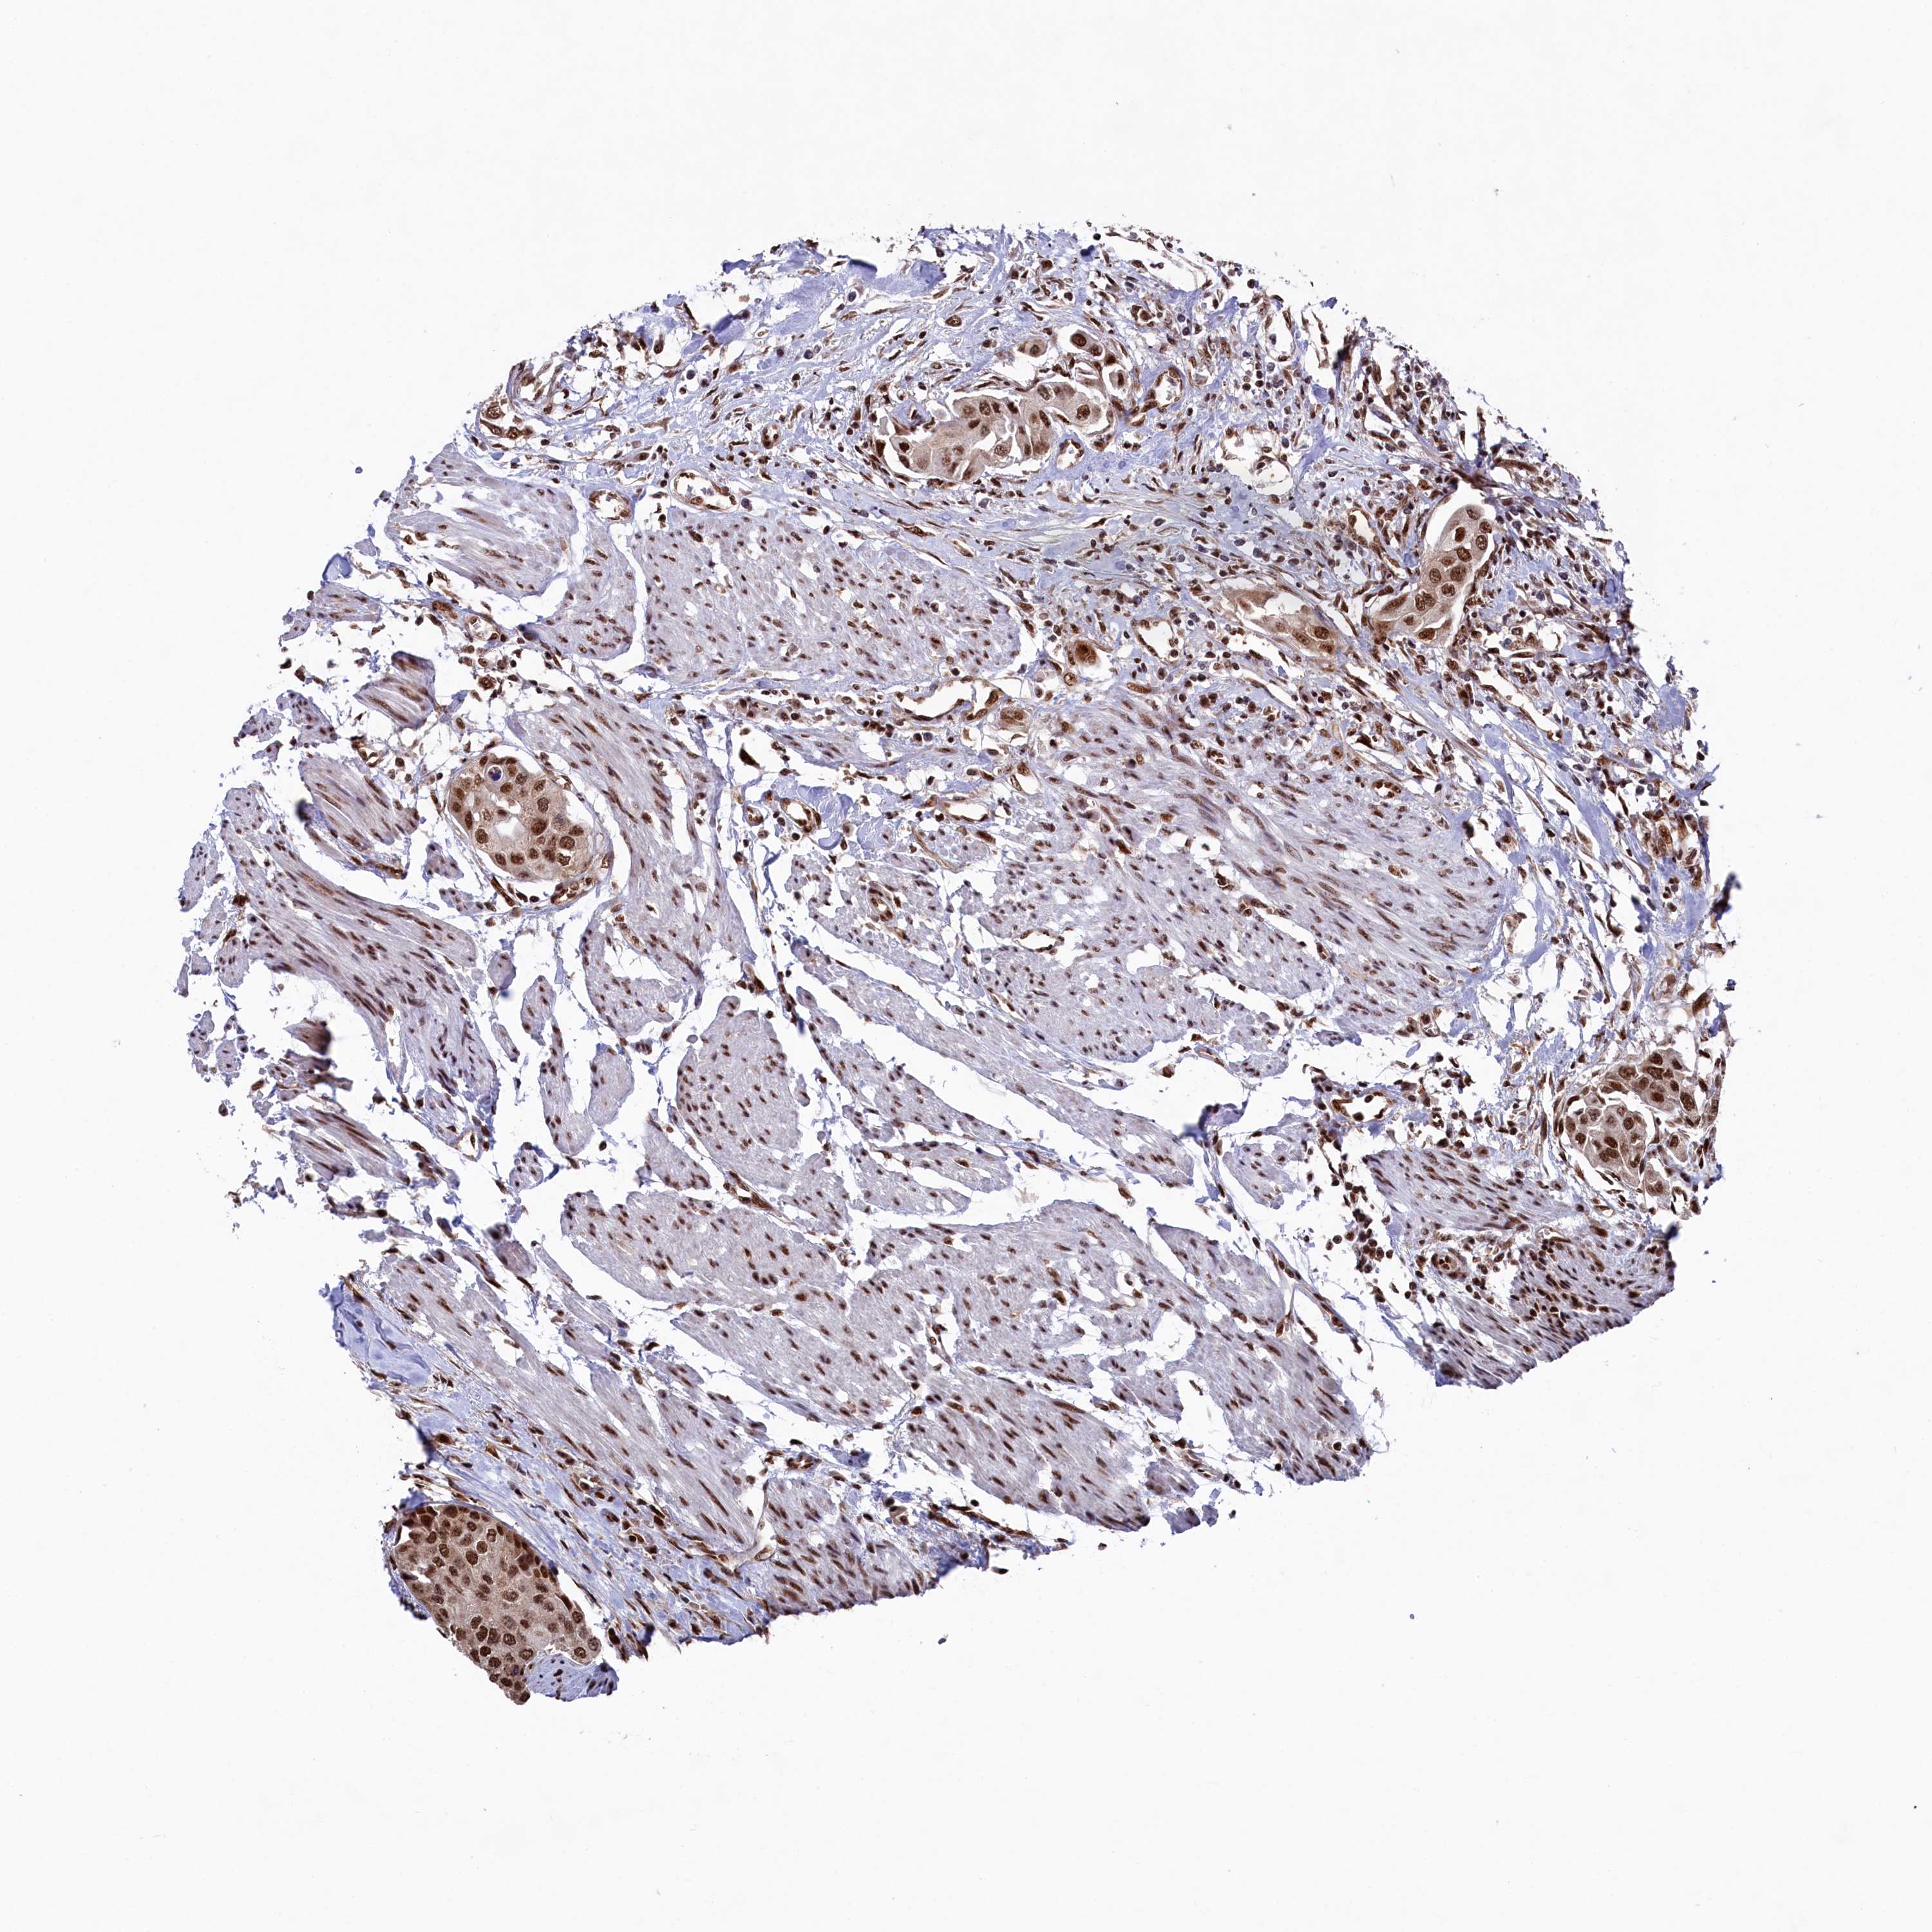

UROTHELIAL CANCER - Protein expressioni

A mouse-over function shows sample information and annotation data. Click on an image to view it in a full screen mode. Samples can be filtered based on level of antibody staining by selecting one or several of the following categories: high, medium, low and not detected. The assay and annotation is described here.

Note that samples used for immunohistochemistry by the Human Protein Atlas do not correspond to samples in the TCGA dataset.

Antibody stainingi

Antibody staining in the annotated cell types in the current human tissue is reported as not detected, low, medium, or high, based on conventional immunohistochemistry profiling in selected tissues. This score is based on the combination of the staining intensity and fraction of stained cells.

Each image is clickable and will lead to virtual microscopy that enables deeper exploration of all samples and also displays staining intensity scores, fraction scores and subcellular localization as well as patient and tissue information for each sample.

Antibody HPA041939

Staining

High

Medium

Low

Not detected

Intensity

Strong

Moderate

Weak

Negative

Quantity

>75%

75%-25%

<25%

None

Location

Nuclear

Cytoplasmic/membranous

Cytoplasmic/membranous,nuclear

Urothelial carcinoma, High grade

Urothelial carcinoma, Low grade

Urothelial carcinoma, NOS